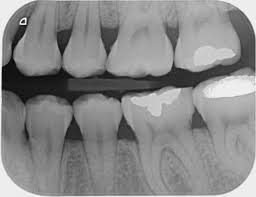

- Radiografías bitewing: El examen ideal para evaluar presencia de caries interproximales. Permite ver las coronas de los dientes superior e inferiores de un lado de forma simultánea.